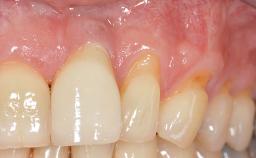

A 30-year-old woman was referred by her general dentist for evaluation of an esthetic complication related to previous implant treatment for congenitally missing maxillary lateral incisors. The patient’s chief complaint was the inadequate esthetic appearance of her smile. The case demonstrates the use of a combined approach to achieve optimal results. Two different flap designs - a tunnel technique and a coronally advanced flap - are employed based on the surgical objectives for the affected site.